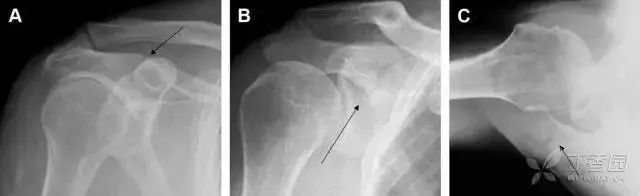

单纯肱骨大结节骨折

与其它肱骨近端骨折不同,单纯肱骨大结节骨折常发生于年轻人。肱骨大结节骨折常由撞击或剪切/撕脱损伤所致:

在常规前后位片上,大结节与肱骨头重叠,骨折不易发现,外旋位前后位片有助于诊断。

图 1 大结节骨折。(A)脂肪抑制序列斜冠状位 MRI,显示肱骨大结节线性骨折无移位(箭头)与周围骨水肿;(B)外旋位前后位(AP)片,证实大结节骨折(箭头),典型的骨折愈合过程中的骨吸收表现;(C、D)初诊时内旋位、外旋位前后位片,初诊时漏诊,仔细回顾影像,内旋伞下可见双密度影(椭圆),骨皮质中断(箭头)